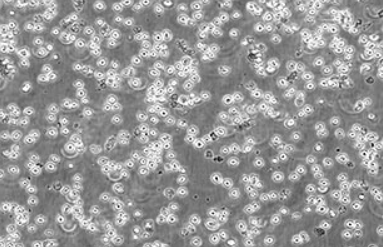

Kasumi-1

80% RPMI-1640+20% FBS

Temperature: 37°C ; Carbon dioxide (CO₂), 5%

悬浮细胞